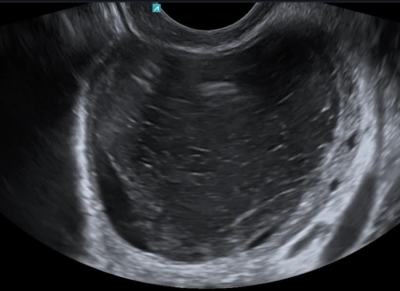

Η διάγνωση είναι εύκολη και μπαίνει με το κλασσικό γυναικολογικό (διακολπικό) υπερηχογράφημα. Συνήθως η ασθενής παρουσιάζει οξύ πόνο ενώ η ρήξη μπορεί, σε κάποιες περιπτώσεις, να οδηγήσει σε ενδοκοιλιακή αιμορραγία. Αν και συνήθως το αιμορραγικό ωχρό δεν λαμβάνει μεγάλες διαστάσεις, αυτό μπορεί να συμβεί σε κάποιες περιπτώσεις.